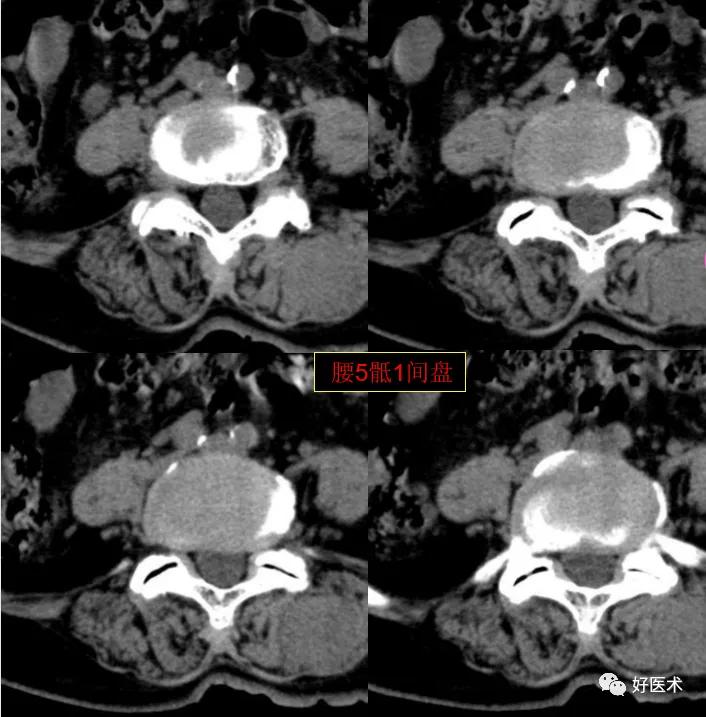

腰5骶1间盘膨隆,双侧椎小关节积气

发现了什么?左侧竖脊肌较右侧明显肿胀饱满, 肌间脂肪间隙消失!!

终于知道了是什么鬼在作乱, 找到了左侧竖脊肌肿胀的元凶:肺癌转移。

- 腰部转移性肿瘤,成骨性及混合型转移,以前列腺癌及乳腺癌多见;溶骨性转移以肺癌多见,多为血行转移,以侵犯椎体及附件骨质为主,进而可波及邻近软组织,而以软组织转移侵犯为首要表现,腰椎体及附件骨质变化不明显的情况,临床及影像上均相对少见。